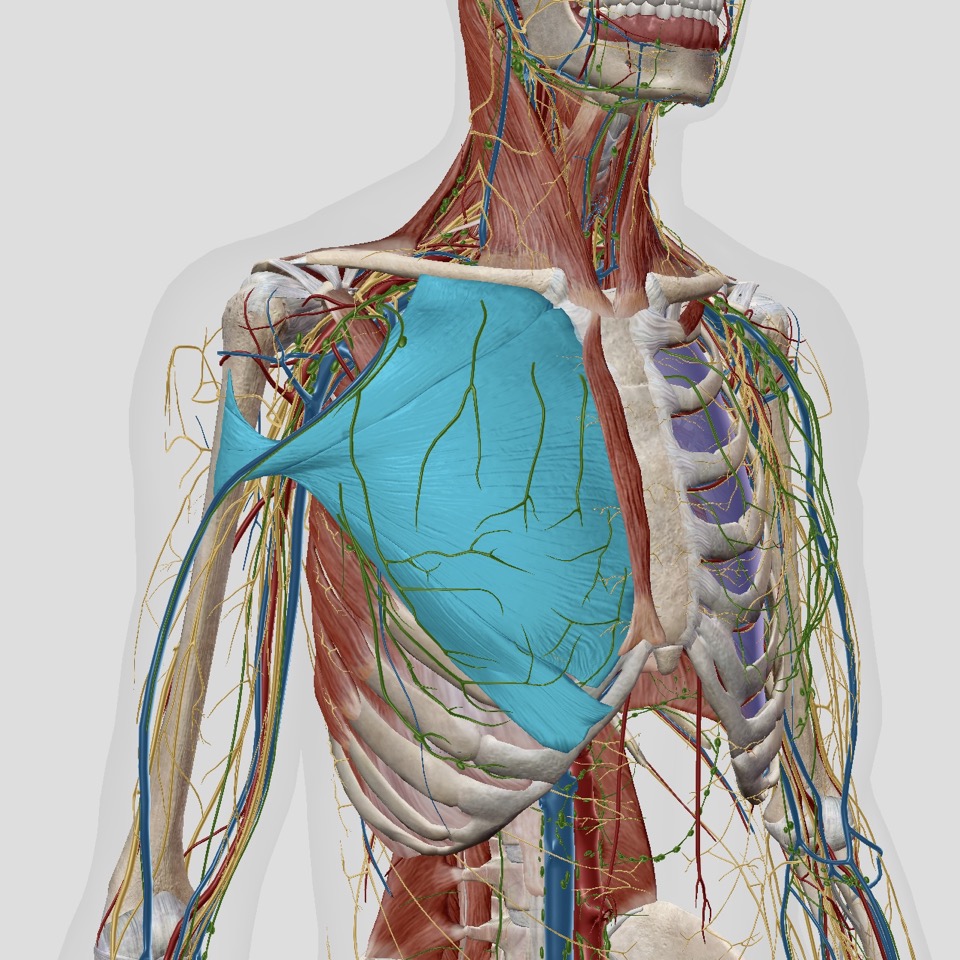

“대흉근”이라고도 알려진 대흉근은 가슴 부위에 위치한 커다란 부채꼴 모양의 근육입니다. 상체의 주요 근육 중 하나이며 일상적인 움직임에 중요한 역할을 합니다. 근육은 밀기, 들어 올리기, 당기기 등 팔, 어깨, 가슴의 움직임을 담당합니다.

대흉근의 해부학적 구조는 여러 부착 지점과 근육 섬유로 인해 복잡합니다. 근육에는 쇄골과 흉골에서 각각 시작되는 3개의 머리(쇄골 머리, 흉골 머리 및 늑골 머리)가 있습니다. 이 세 개의 머리가 만나 상완의 상완골에 부착되는 단일 힘줄을 형성합니다.

대흉근은 근육에 감각 및 운동 기능을 제공하는 내측 및 외측 흉부 신경의 지배를 받습니다. 대흉근의 근육 섬유는 대각선으로 배열되어 있어 근육이 수축하고 여러 방향으로 힘을 생성할 수 있습니다.